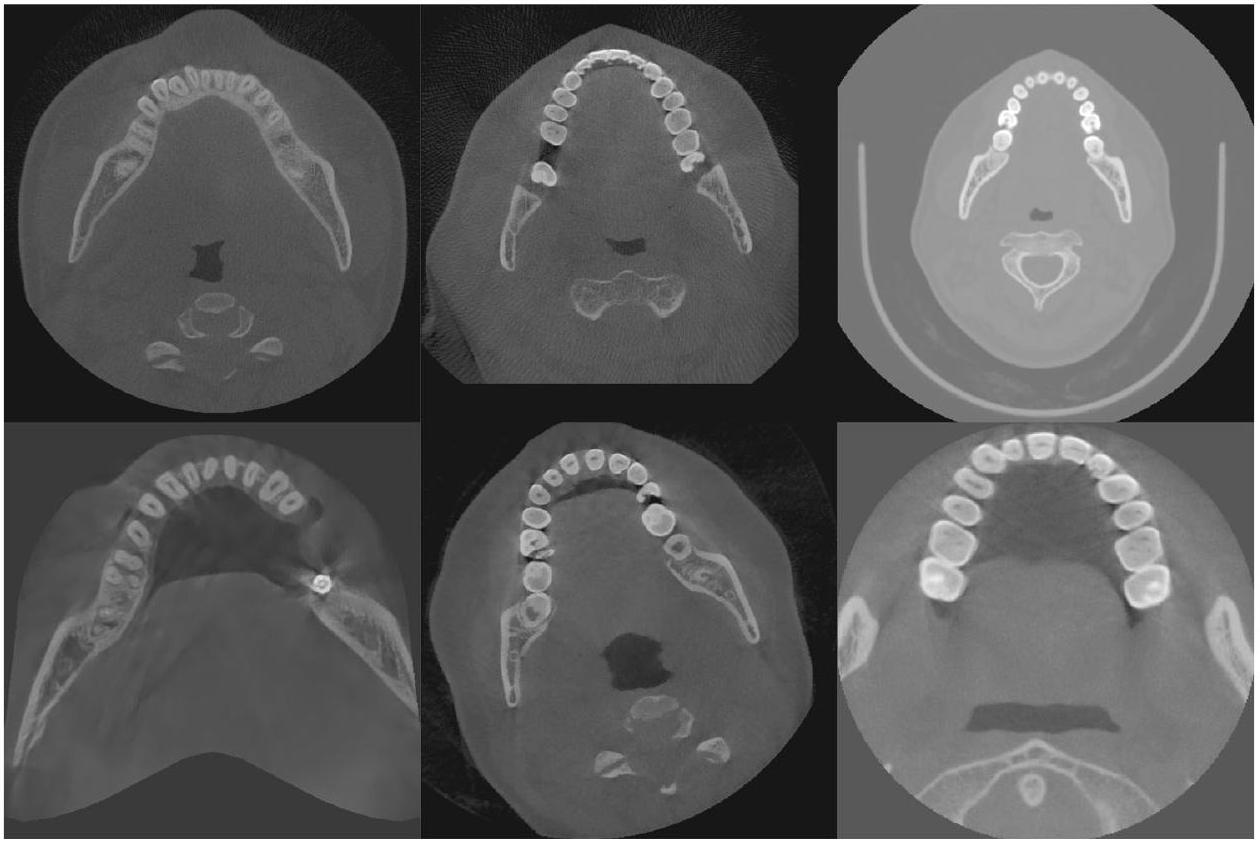

طرق المعالجة المسبقة لجميع صور CBCT؛ وفي مهمة تقسيم الأسنان، فإن معظم الصور الأصلية هي مناطق أنسجة لينة غير مفيدة للتقسيم، مما يؤدي إلى توزيع غير متوازن للبيانات، وهو ما لا تعالجه الطرق الحالية. تُظهر الصور الفعلية لـ CBCT في الشكل 2، ويمكن ملاحظة وجود اختلافات كبيرة في تباين الصورة، ومجال الرؤية، وما إلى ذلك. - الطرق الحالية معقدة للغاية وغالبًا ما تتطلب خطوات متعددة للحصول على نتائج تقسيم جيدة. قد تتطلب هذه الطرق استخدام تقنيات معالجة مسبقة متعددة، وطرق استخراج الميزات، والمصنفات أو النماذج، وخطوات المعالجة اللاحقة لإكمال تقسيم الأسنان. تؤدي هذه التعقيدات إلى طرق أقل كفاءة من الناحية الحسابية، حيث قد يقدم كل خطوة أخطاء أو عيوب، وكل خطوة في العملية الكاملة تتطلب ضبطًا دقيقًا وتحققًا، مما يزيد من صعوبة تطوير الطرق وتطبيقها.

preprocessing methods to all CBCT images; and in the tooth instance segmentation task, most of the original images are soft tissue regions that are not useful for segmentation, resulting in an unbalanced distribution of data, which is not addressed by the current methods. The actual CBCT images are shown in Fig. 2, and it can be seen that there are large differences in image contrast, field of view, etc. - Existing methods are too complex and often require multiple steps to obtain good segmentation results. These methods may require the use of multiple preprocessing techniques, feature extraction methods, classifiers or models, and post-processing steps to complete the segmentation of teeth. This complexity leads to less computationally efficient methods, each step may introduce errors or mistakes, and each step in the whole process requires careful tuning and validation, which increases the difficulty of method development and application.